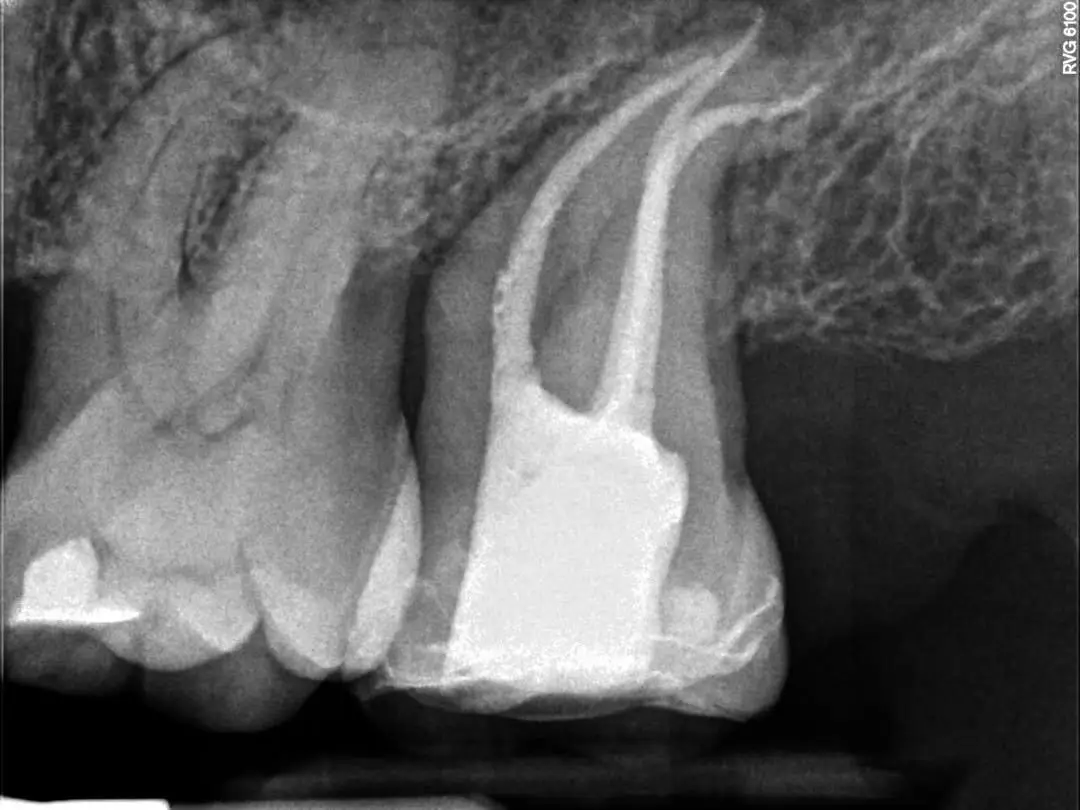

See the Difference Specialist Care Makes

Compare real treatment results through detailed before-and-after X-rays, showing how expert care restores dental health, precision, and long-term outcomes.